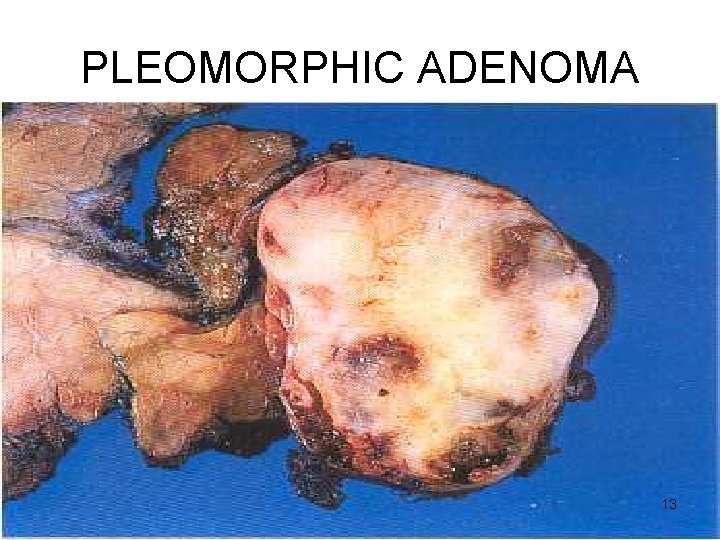

PLEOMORPHIC ADENOMA Gross • < 6 cms • Bosselated • Well-demarcated / encapsulated / tongue-like protrusions • Cut surface: gray-white / variegated / myxoid / bluish translucent (chondroid) 11

PLEOMORPHIC ADENOMA 13